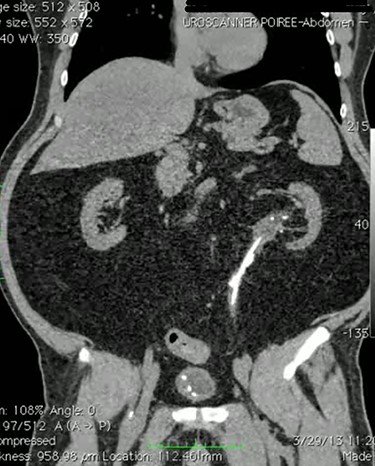

This is a case of 48-year-old man Hypertensive on medication who underwent bilateral percutaneous nephrolithotomy 10 years ago for bilateral renal stones. Patient was referred to our center as a case of left ureteric injury post Flexible URS for left middle and upper ureteric stones and was managed with left DJ stent. Abdominal CT scan showed stones in the left ureter with no leak (Fig. 1). Two months later, we decided to perform retrograde pyelography (RGP) and eventually ureteroscopy in order to clear his stones. RGP showed an invagination of mid-ureter about 4–5 cm (Fig. 2). A guidewire was passed under fluoroscopy guidance. Stones were removed and endoscopic exploration revealed ureteral intussusception (Fig. 3). DJ stent was inserted, and 6 weeks later, we performed a nuclear scan (MAG3) that showed obscure drainage from the left kidney. Therefore, ureteral reconstruction with ileal interposition was our option to overcome this complication. Patient underwent the surgery uneventfully and was followed up after surgery for 6 months and was pain free with no significant hydronephrosis or change in renal function.

Endoscopic image during ureteroscopy showing ante-grade invagination of the ureter.